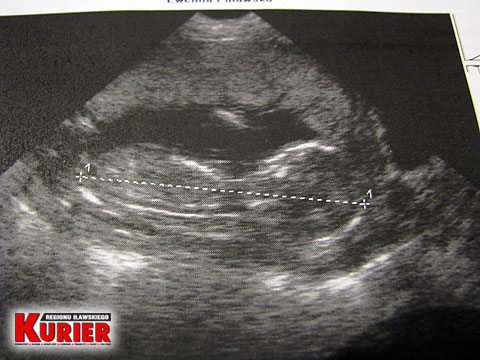

Tak wyglądał Olek w 14. tygodniu życia płodowego.

Już wtedy jego Mama nie miała żadnych

wątpliwości, że powinna go urodzić.